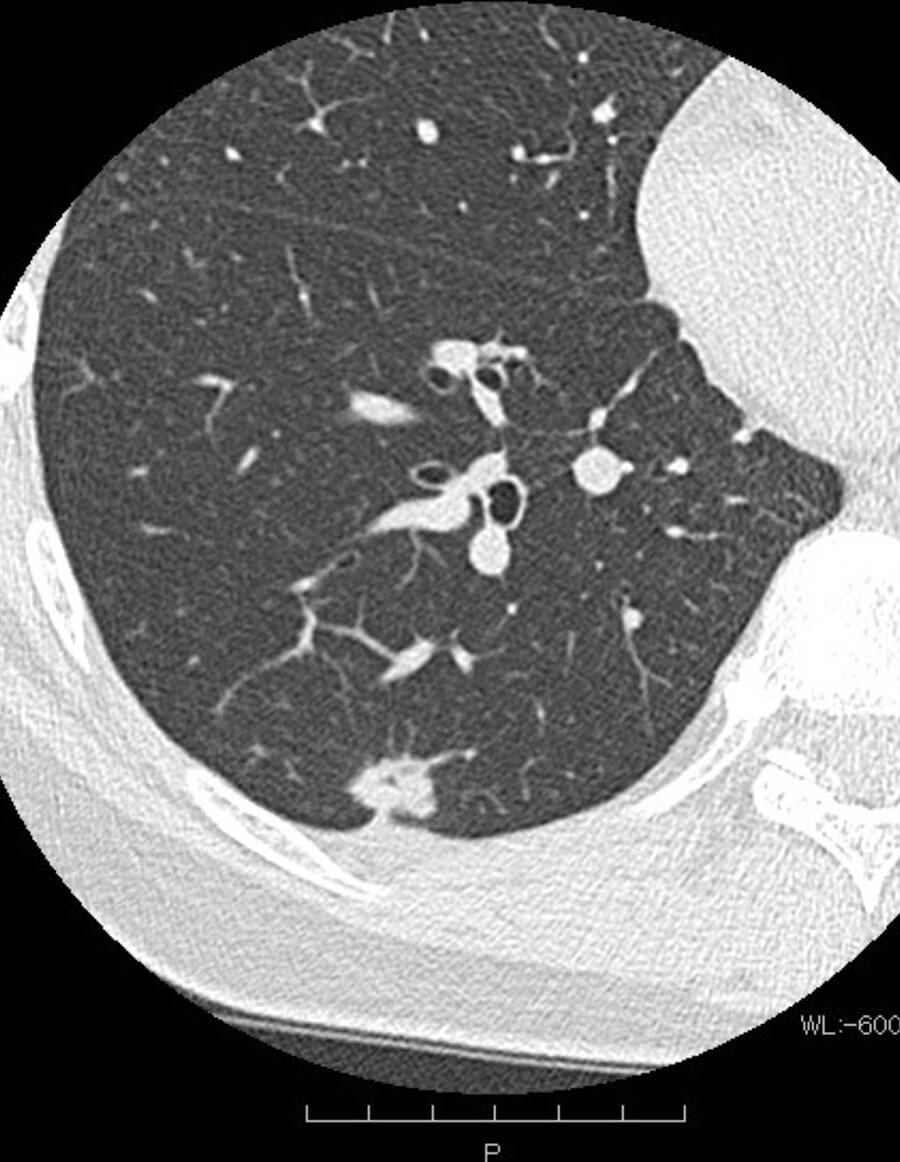

呼吸器疾患の検査には、胸部CT検査はとても有効です。CTではコンピューターで処理して体の輪切り像を作り、立体的かつ断層的に肺や気管支、縦隔、胸膜など胸部内の構造を詳細に映し出します。数ミリの小さな結節といったX線撮影では見逃されがちな小さな病変も捉えることができ、肺癌の早期発見に非常に役立つとされています。特に無症状で進行する肺癌を早期に発見するためには、CT検査は欠かせません。

肺気腫

肺胞が破壊されて空気のたまり(ブラ)が形成され、肺の構造が壊れる状態です。CTでは肺の一部が黒く抜けたように見えます。肺の容積が大きくなって密度が低下することにより、たまった空気を押し出せなくなり、肺でのガス交換が困難になり、息切れや慢性的な咳などの症状が現れるようになります。慢性閉塞性肺疾患(COPD)の特徴的な一形態とされています。

結節影・腫瘤影

結節影とは肺の中にできた直径3cm以下小さな塊のような影で(3cmより大きいものは「腫瘤影」と呼ばれます)、大きさや形状、境界の明瞭さによって悪性の可能性を評価し、必要に応じて追加検査が行われます。肺癌が疑われる場合は速やかに高次機能病院へご紹介をさせて頂きます。